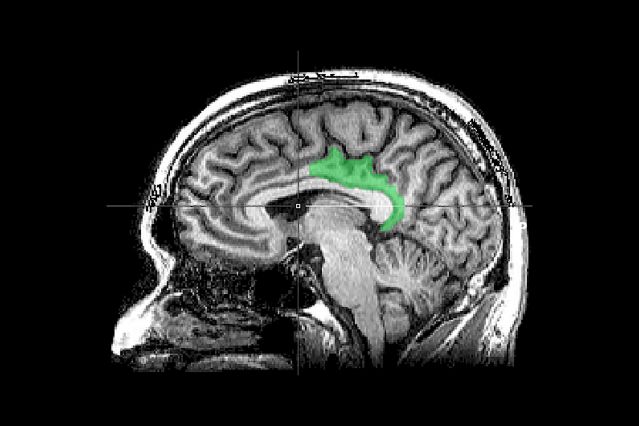

Sagittal MRI slice of a mind with highlighting indicating the locale of the posterior cingulate cortex. The research cited uncovered traumatic memories engaged this area, typically related with narrative comprehension and autobiographical processing, like introspection and daydreaming.

Supply: Geoff B. Hall/Inventive Commons CC0 1.